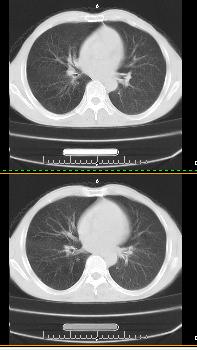

以下是引用liaoqiang在2008-3-21 17:45:00的发言:[br]右上叶尖段、后段有多发小结节和小条状影。考虑感染(结核可能性大。)。建议治疗后复查。

以下是引用王2008在2008-3-21 17:38:00的发言:[br]右上叶后段沿纹理走向呈串珠状.边缘欠清密度增高影,局部胸膜增厚.[br]考虑1.右上支扩可能.2.右上炎症.建议治疗后复查.请各位老师指教.

以下是引用lj11119999在2008-3-21 18:15:00的发言:[br]右上叶尖段、后段有多发小结节和小条状影。考虑感染(结核可能)建议进一步检查!